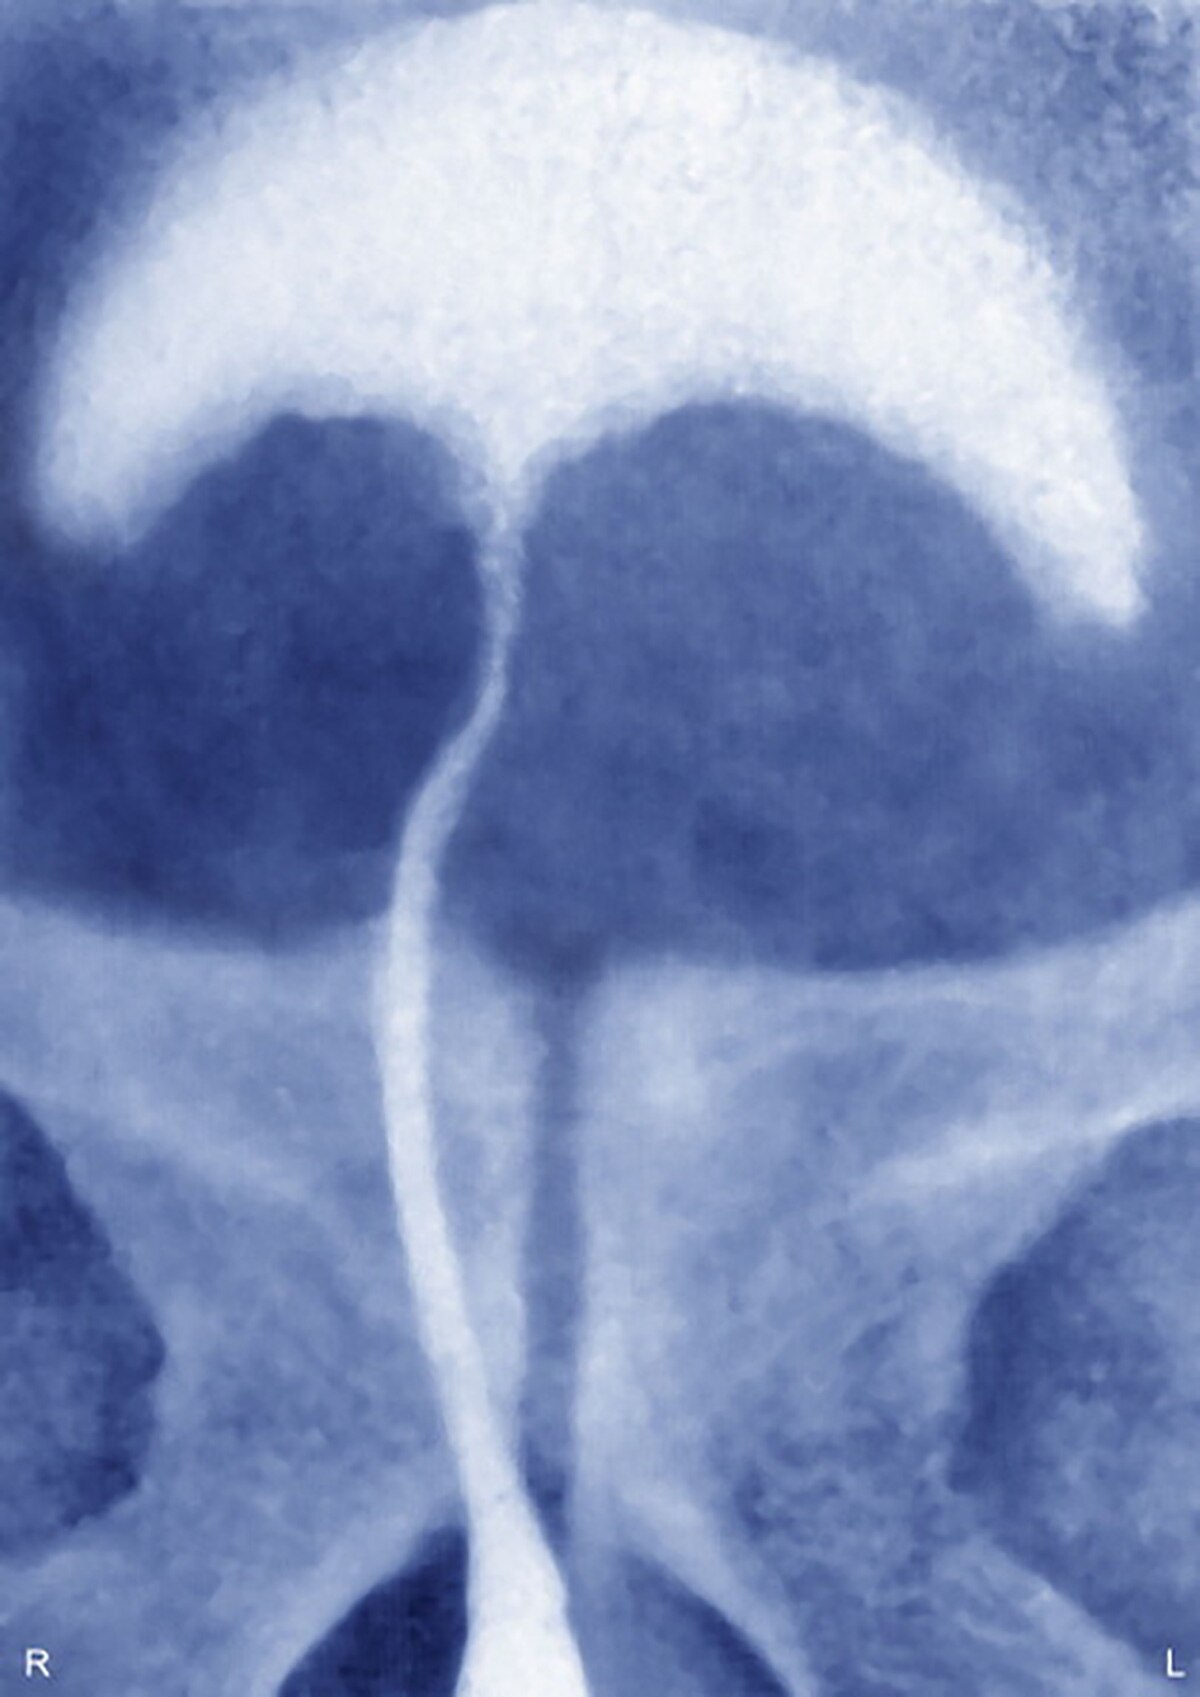

मिशिगन के स्पैरो हॉस्पिटल में इस शख्स को गंभीर हालत में भर्ती कराया गया था. वह दर्द से कराह रहा था और पेशाब भी नहीं कर पा रहा था. जब डॉक्टरों ने चेक किया तो पता चला कि शख्स के प्राइवेट पार्ट में राजमा के 6 दाने फंसे हैं.

डॉ. मार्गो डेनिस ने बताया कि पेशाब नली में राजमा के दाने फंसे हुए थे. हालांकि शख्स ने इन्हें घर पर भी निकालने का प्रयास किया था, लेकिन वह सफल नहीं हुआ. (प्रतीकात्मक फोटो/Getty images)